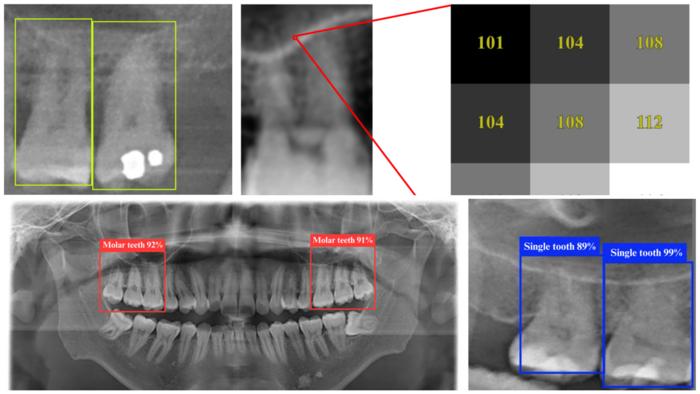

Sample dental panoramic radiographs (DPRs) as seen by the YOLO 11n deep learning model, which is able to identify tooth structures with up to 98.2% accuracy.

Pei-Yi Wu et al., 2025